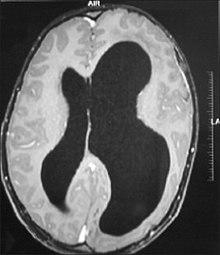

| An MRI of a patient with benign familial macrocephaly (male with head circumference > 60cm) | |

Macrocephaly is a condition in which the human head is abnormally large; this includes the scalp, the cranial bone, and the contents of the cranium. It may be pathological or benign, even a familial genetic characteristic. People diagnosed with macrocephaly will have further testing done to determine whether the syndrome is accompanied by any other disorders. Those with benign or familial macrocephaly are considered to have megalencephaly, another form of macrocephaly that will not result in the development of neurological disorders in the patient.

Many people with abnormally large heads or large skulls are healthy, but macrocephaly may be pathological. Pathologic macrocephaly may be due to megalencephaly (enlarged brain), hydrocephalus (abnormally increased cerebrospinal fluid), cranial hyperostosis (bone overgrowth), and other conditions. Pathologic macrocephaly is called "syndromic", when it is associated with any other noteworthy condition, and "nonsyndromic" otherwise. Pathologic macrocephaly may be caused by congenital anatomic abnormalities, genetic conditions, or by environmental events.[1]